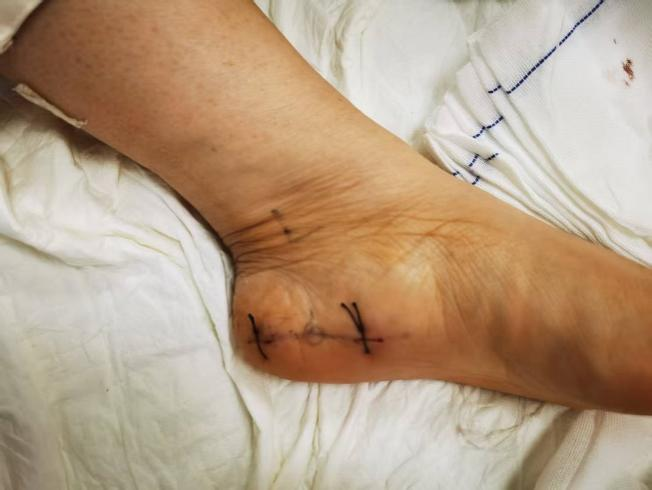

手术微创切口

2 创伤极小,美观无痕

相比传统手术的长切口,微创治疗仅需几个小孔,对周围正常的肌肉、血管和神经组织干扰极小,几乎不留疤痕,满足了现代人对美观的追求。